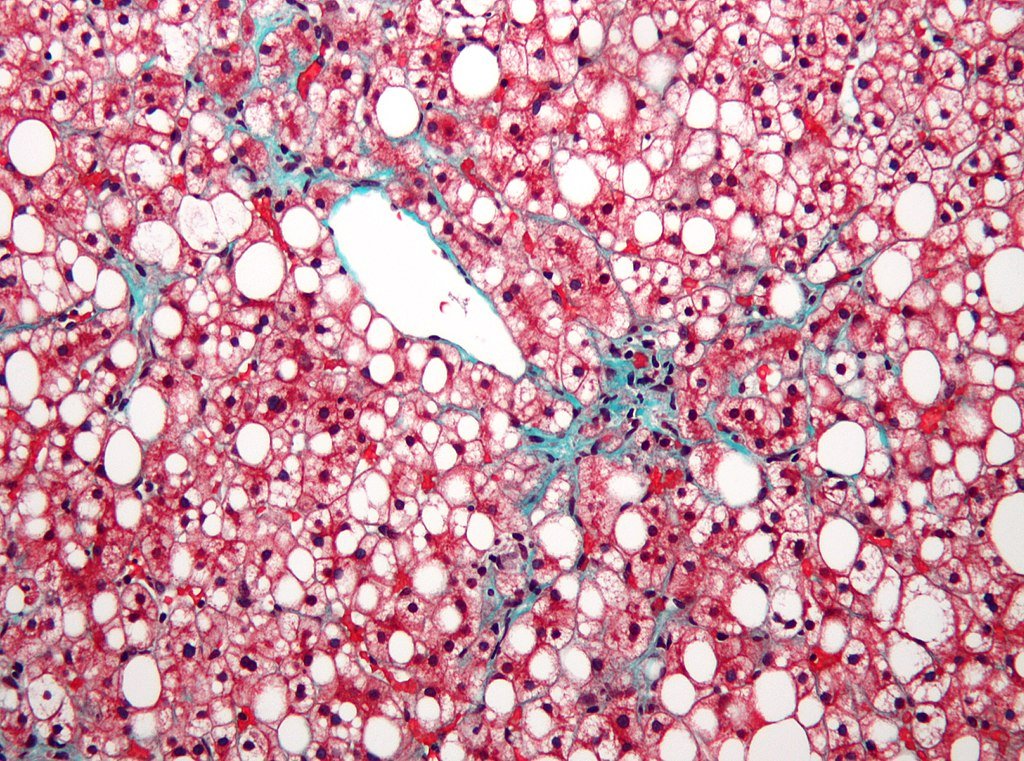

Nephron, CC BY-SA 3.0 https://creativecommons.org/licenses/by-sa/3.0, via Wikimedia Commons

Researchers have found an unlikely hero in the fight against one of the world’s most common and stubborn liver diseases, an unsuspecting gut fungus. New research suggests that Fusarium foetens, a bacterium found in the human gut, may hold the key to treating metabolic-dysfunction-associated fatty liver disease (MAFLD), which afflicts over 1 in 4 adults globally.

The findings, published May 1 in Science, reveal how this overlooked fungus reduces liver fat, inflammation, and scarring in mice raising hopes for a future human treatment. But how did researchers stumble upon this potential breakthrough, and why has gut fungi remained a mystery for so long?